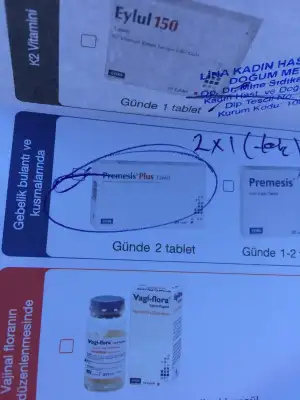

Kızlarr biz de doktordan çıktık minnoşum 9+1 olmuş ve kalbini de duydukdünyanın en tatlı sesiydi galiba

Bulantılarım için folik asidimi değiştirdi ve zencefil önerdi iyi geliyormuş

Hepimize teşekkür ederim kızlar 8 hafta sanıyorken 9 çıkmasına çok sevindim :)

Folidoce kullanıyordum premasis plus şimdi verdiğinin adı. Bebek çok minnoştu baya şekillenmiş ama hatta size ultrasonunu ekleyeyim

Folik asidi de ekliyorum :) zencefili kaynar suya 1 dilim atıp suyu içebilirmişiz. Toz olanıda yoğurtla yiyebilirsin dedi

Canım gözün aydın senin geç döllenmeydi demi? Şimdi haftasını yakaladı mı?Hepimize teşekkür ederim kızlar 8 hafta sanıyorken 9 çıkmasına çok sevindim :)

Folidoce kullanıyordum premasis plus şimdi verdiğinin adı. Bebek çok minnoştu baya şekillenmiş ama hatta size ultrasonunu ekleyeyim

Folik asidi de ekliyorum :) zencefili kaynar suya 1 dilim atıp suyu içebilirmişiz. Toz olanıda yoğurtla yiyebilirsin dedi